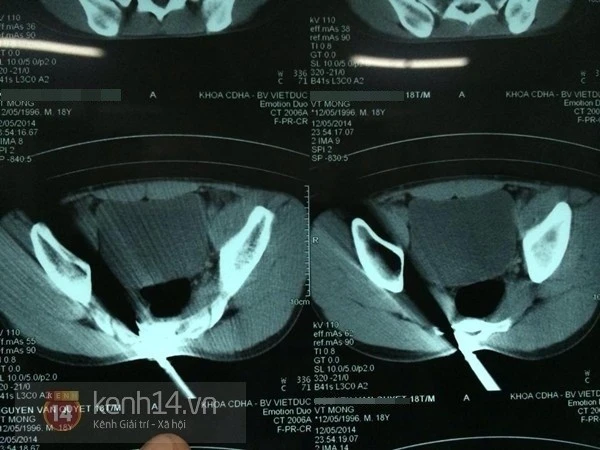

Sau khi được đưa vào viện, bệnh nhân đã được các bác sĩ điều trị và tiến hành mổ cấp cứu. Hình ảnh chụp phim cắt lớp cho thấy đầu nhọn của dị vật đã xuyên qua xương cùng ra tận thành trước, tuy nhiên, rất may là không bị thủng trực tràng.

Hình ảnh chụp phim cắt lớp.